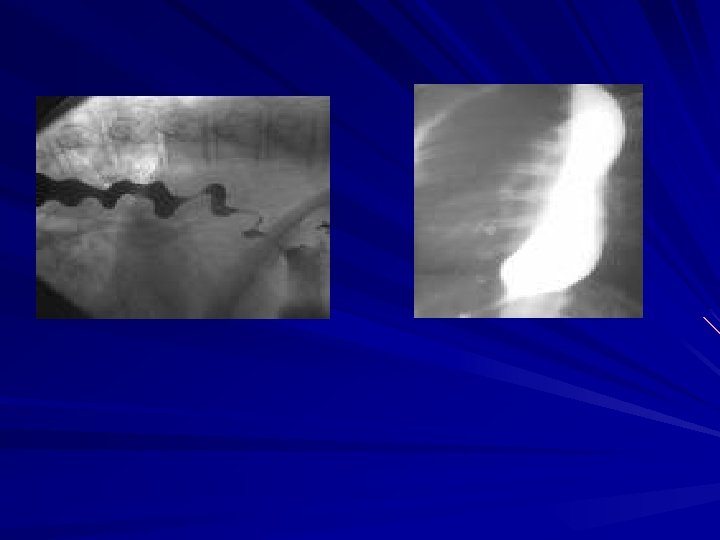

Esophageal Motility Disorders Diagnosis Ø History Ø Physical examination-unremarkable Ø Barium Swallow Bird peak appearance- classic for achalasia Rosary beads or corkscrewclassic for DES

Achalasia